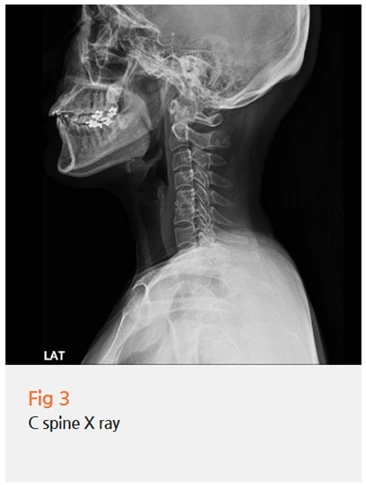

다음으로 경추 X-ray를 촬영했습니다.

이 환자분은 과거에 목 디스크 치료를 받으신 이력이 있으셨고,

경추부 정렬 상태를 확인했을 때 경추 주변 긴장이 상당히 있는 상태였어요.

경추 주변 근육과 신경이 과도하게 긴장되면 교감신경 긴장도가 높아지는데,

이게 안면 신경과 눈 주위 근육까지 영향을 줄 수 있어요.

눈둘레근은 안면신경의 지배를 받는 근육인데,

교감신경이 흥분 상태가 되면 이 부위도 함께 예민하게 반응하게 되는 거예요.

즉, 목의 긴장이 자율신경을 통해 눈 주위 근육의 과민 반응으로 이어지는 겁니다.

이 환자분의 경우, 바로 그 패턴이었어요.

경추부 긴장과 자율신경 이상이 주된 원인으로 작용하고 있었고,

동측 후두부 두통과 안구통도 이와 연결되어 있었습니다.